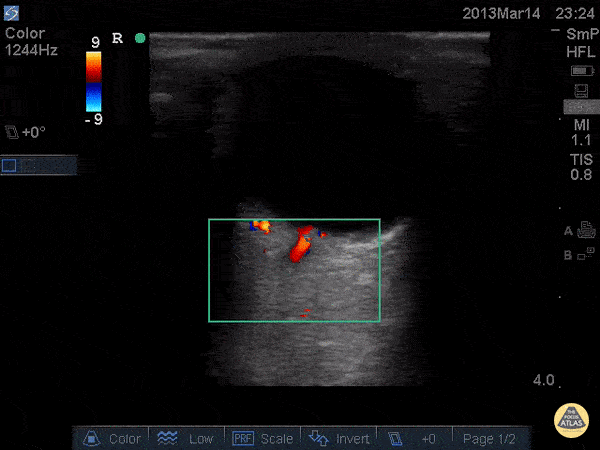

Orbital - Central Retinal Artery and Venous Flow - Normal

Venous and arterial flow can be seen in this color flow doppler image. Dr. Joshua Schechter - SUNY Downstate/Kings County Emergency Medicine